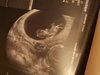

Z USG wszystko ok maluch ma 27,77mm co odpowiada na 9+3 czyli tak jak mam to zostaje na 21.09 maluch się ruszał machał rączkami i nóżkami fajne to uczucie :* najbardziej mnie zaniepokoił słaby sprzęt ale ważne że było widać :*